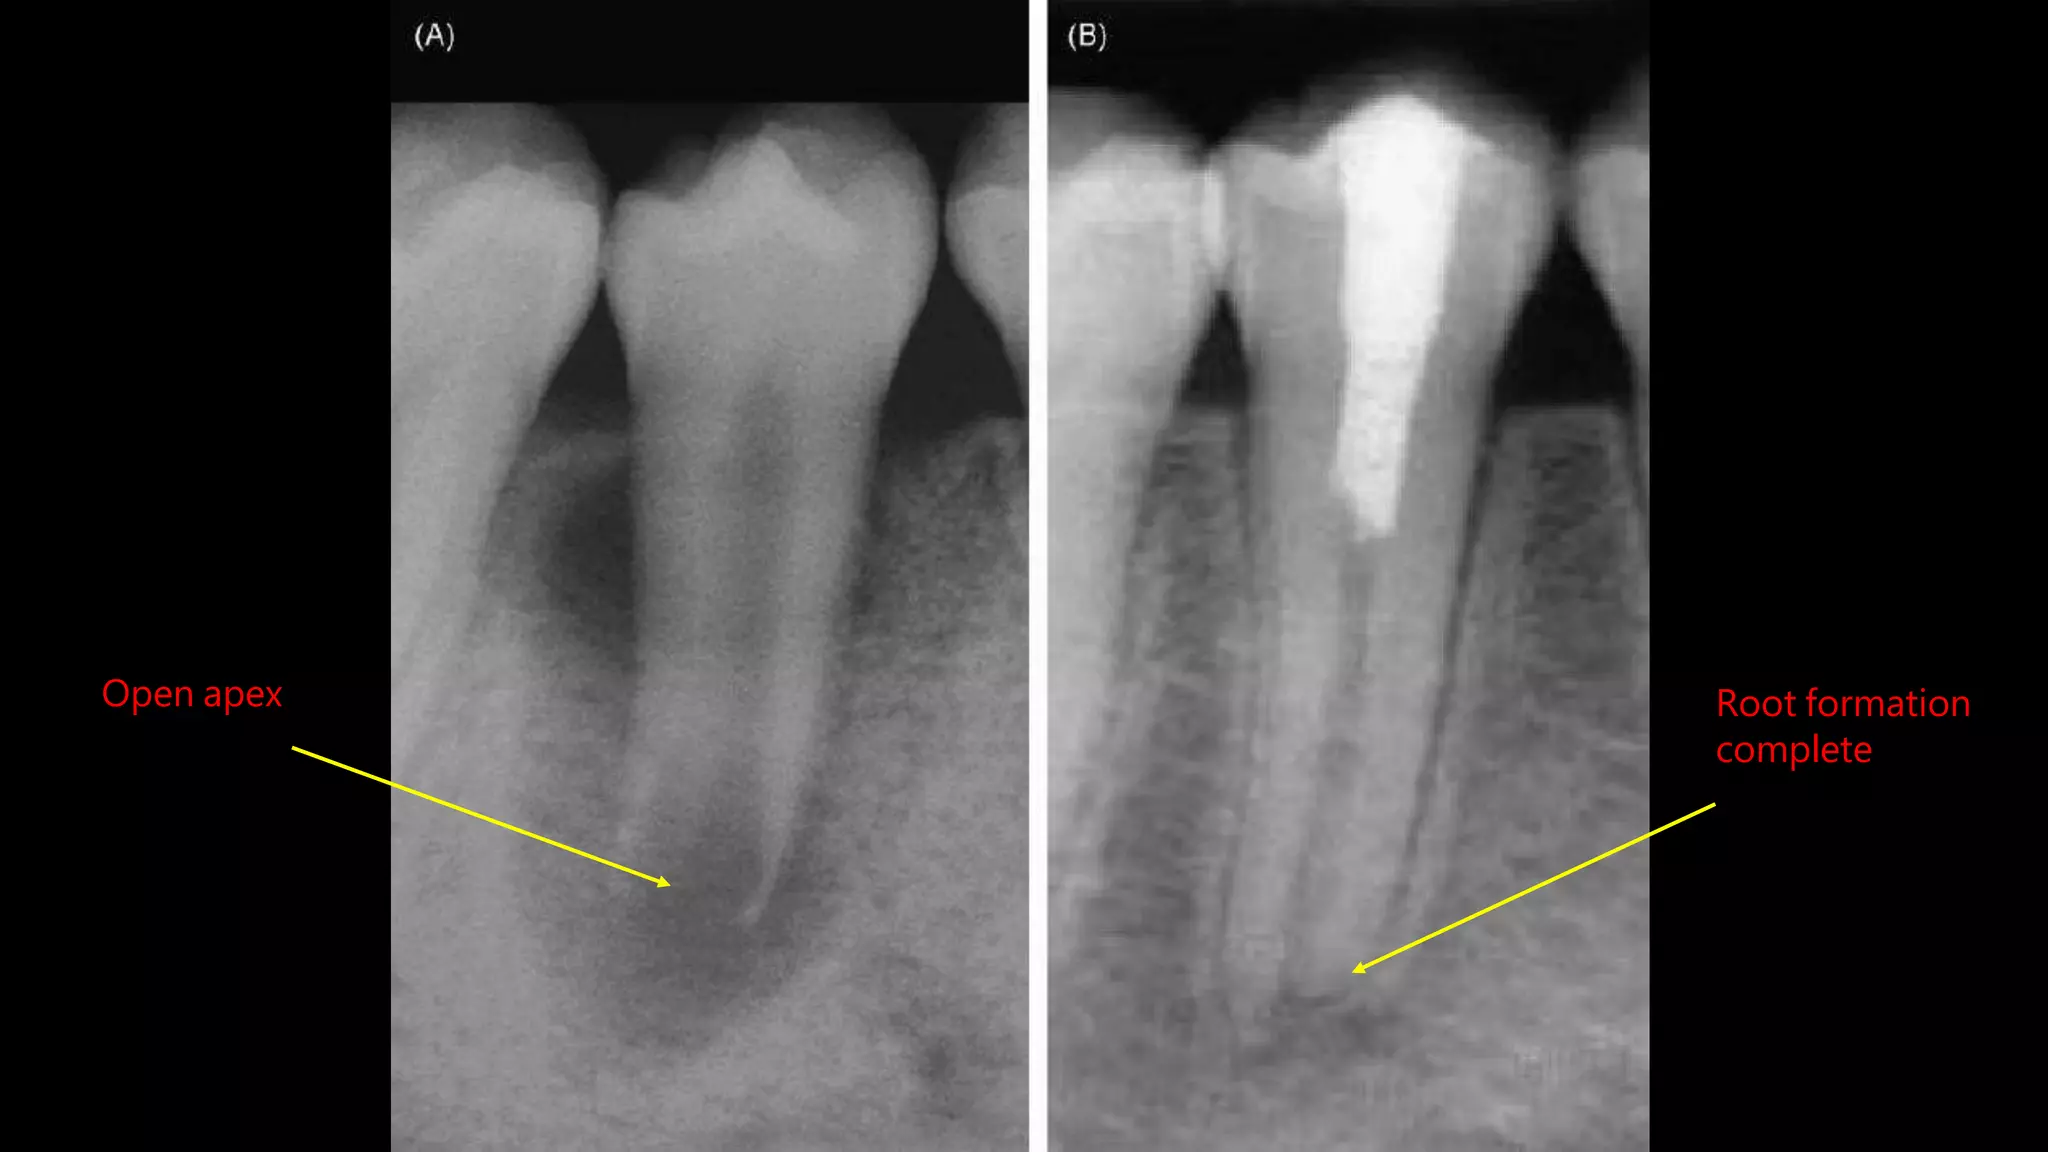

Open apex Root formation

complete

Open apex Rootformation complete